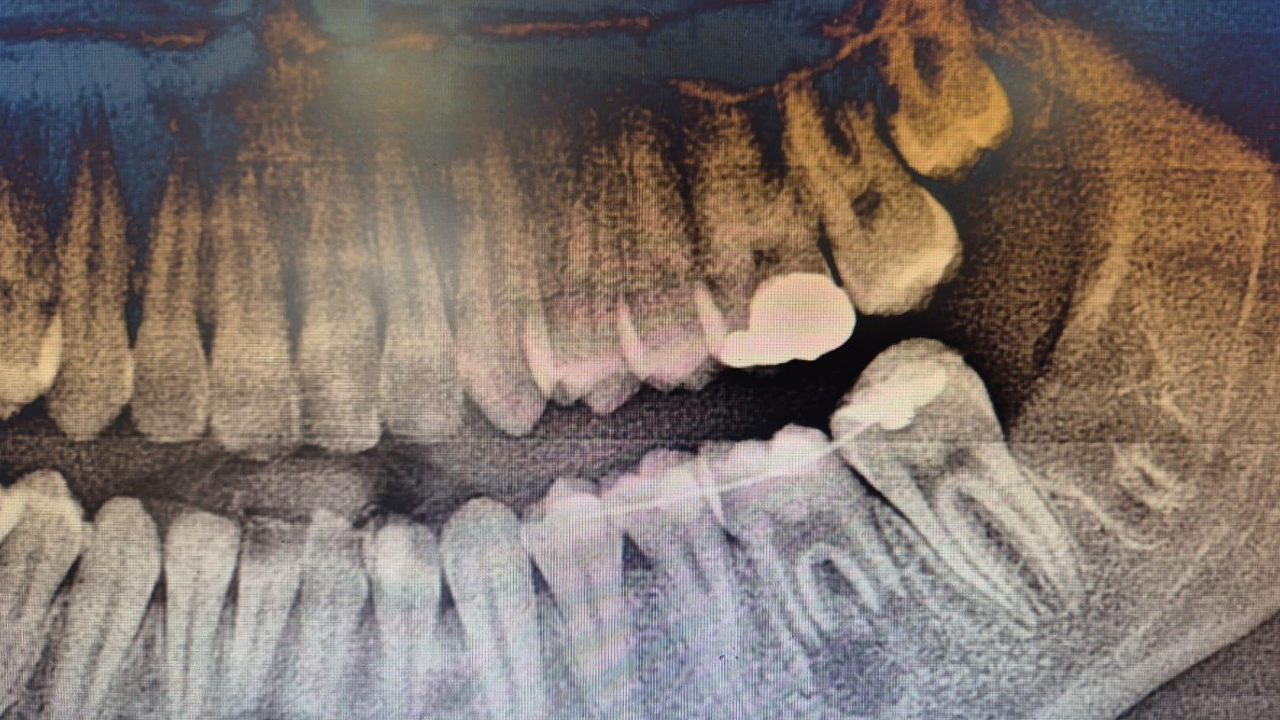

İleri düzey çürük nedeniyle bir daimi azı dişi çekilen hastada, çene gelişimi devam ettiği için implant gibi klasik tedavi yöntemleri uygun bulunmadı. Bunun üzerine uzman hekimler, hastanın kendi ağzında kemik içinde gömülü bulunan üçüncü azı dişini (yirmi yaş dişi) operasyon mikroskobu eşliğinde çıkararak, çekilen dişin yerine nakletti.

Tedavi sırasında ayrıca hastanın kendi kanından elde edilen PRF (Platelet Rich Fibrin) materyali, diş yuvasına uygulanarak doku yenilenmesinin hızlanması sağlandı. Bu sayede dişin hem daha sağlıklı bir şekilde tutunması hem de iyileşme sürecinin kısalması hedeflendi.